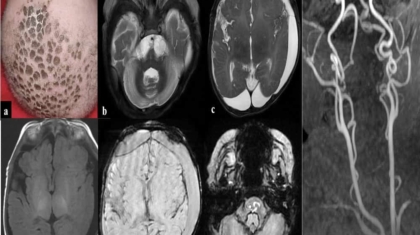

A 5month old male child born out of by non-consanguineous marriage presented with history of left focal seizure, reddish discoloration of left hand and delayed attainment of milestones. Parents also noticed increase in fairness of the baby and loss of hair.